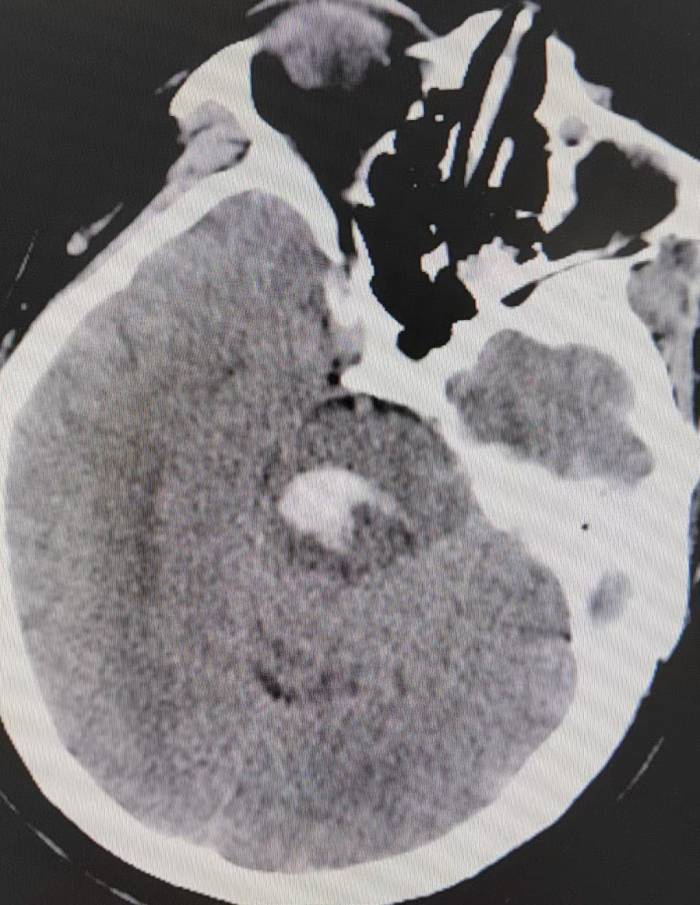

患者3月30日头颅CT平扫结果显示其右侧脑干出血